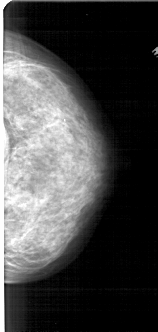

A_1755_1.RIGHT_CC

RIGHT_CC LINES 4966 PIXELS_PER_LINE 2356 BITS_PER_PIXEL 12 RESOLUTION 43.5 NON_OVERLAY